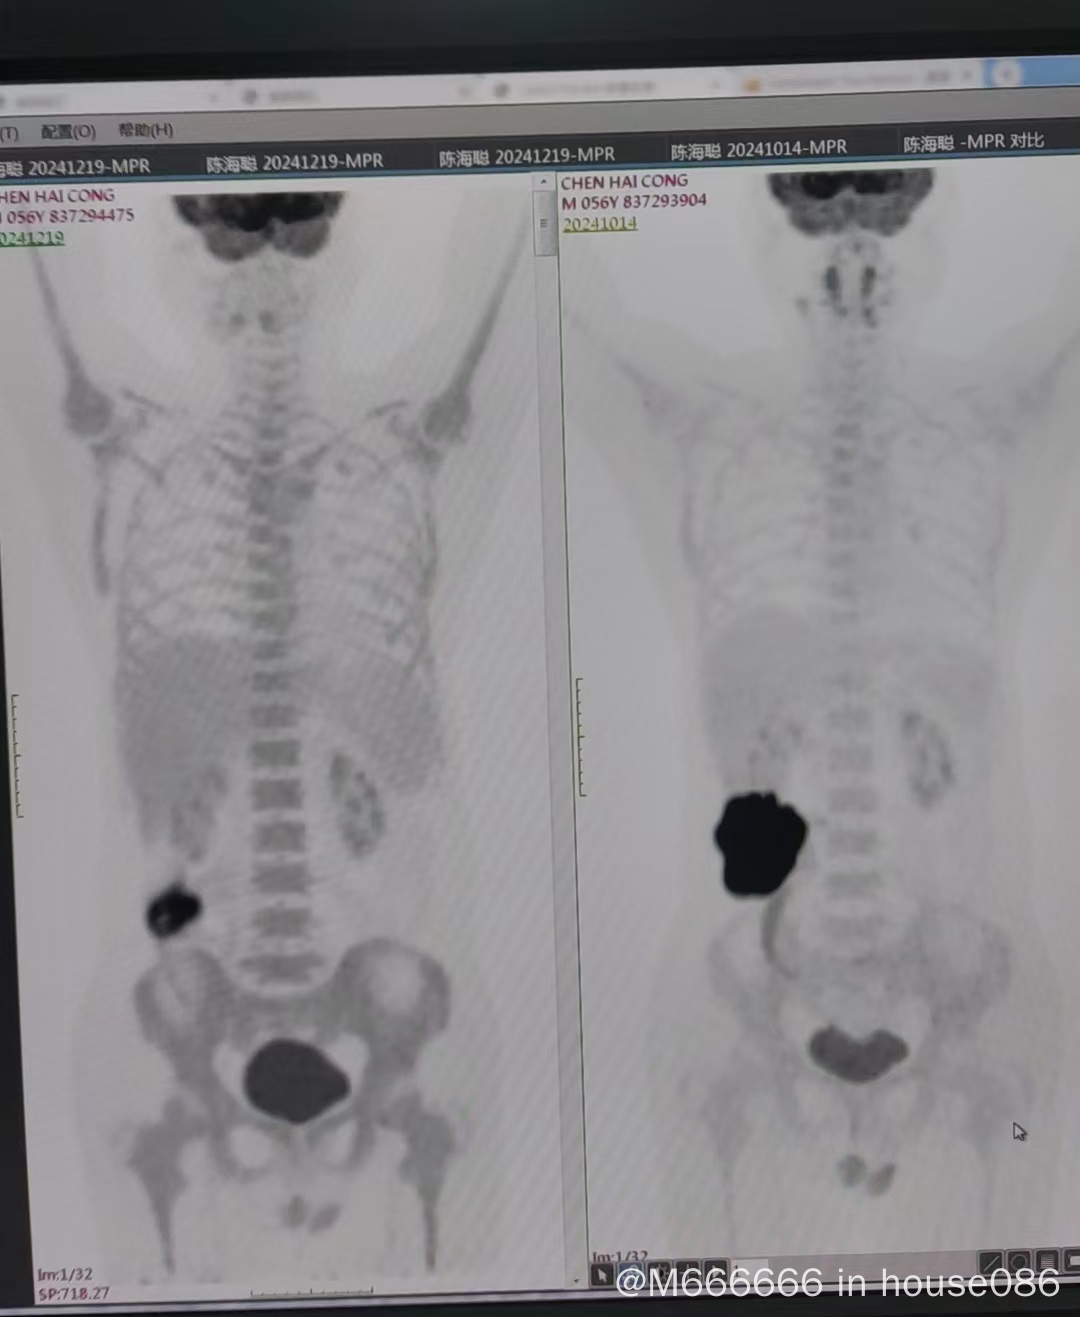

hyper CAVD AB三疗后中期评估5分,回盲部肿瘤较前缩小,代谢值降低,医生建议先手术切除继续化疗?求助大神们帮忙看看这个方案可取吗?